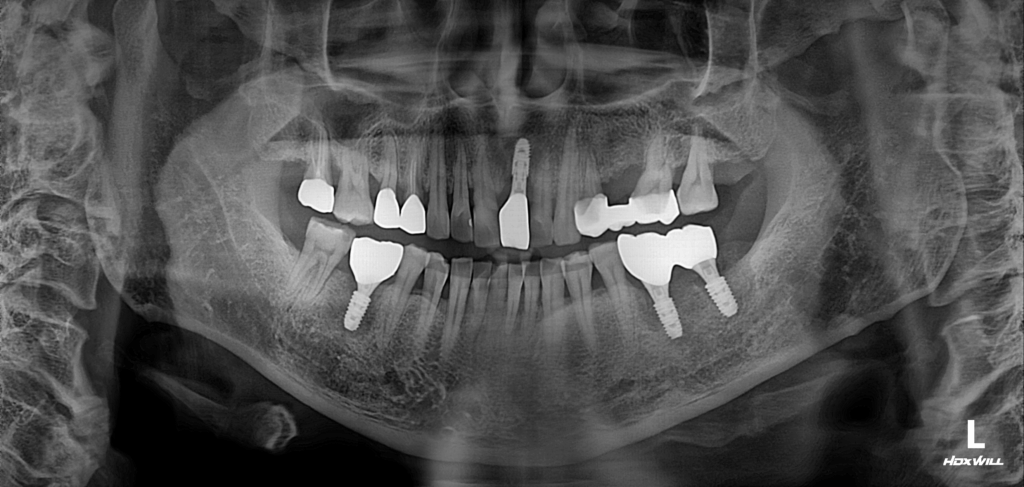

25.07

필요한 부위에만 임플란트를 정밀하게 식립한 결과를 확인할 수 있습니다. 하악 구치부는 앞서 언급한 바와 같이 해부학적 특성을 충분히 고려하여 접근해야 합니다.

이 케이스에서는 하악신경관과의 안전한 거리를 계산하여, 후유증이 발생하지 않도록 세심하게 진행했습니다. 지속적인 추적 관리로 신경 손상 여부를 면밀히 모니터링했으며,

결과적으로 환자분은 후유증 없이 정상적인 기능을 회복하며 만족스러운 결과를 얻으셨습니다.